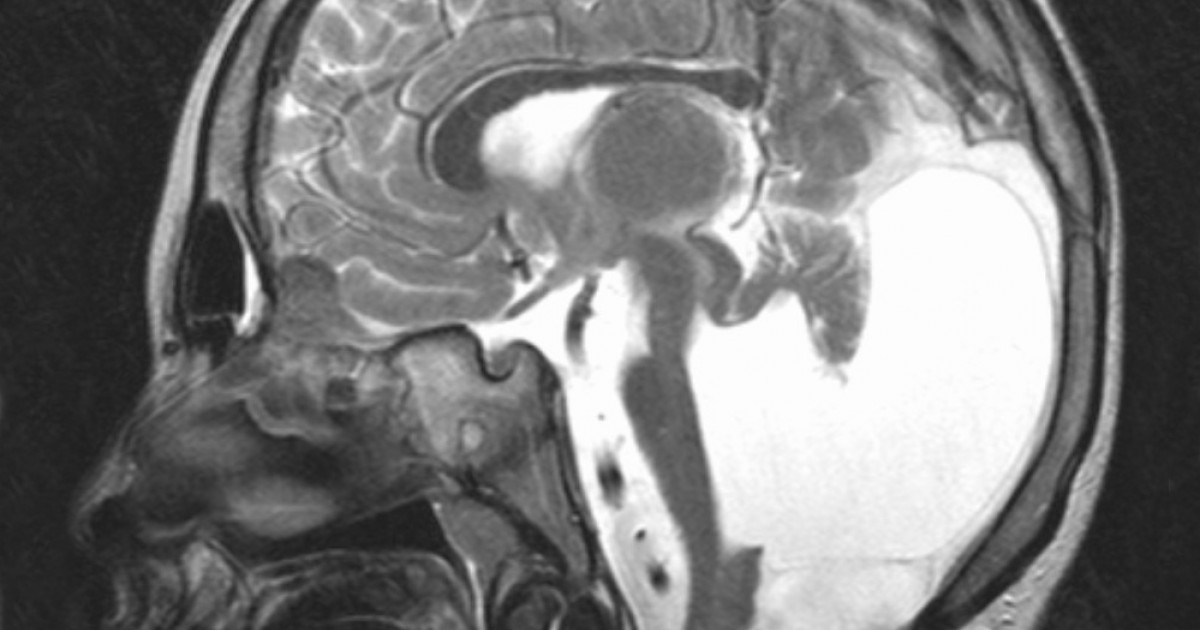

Денди уокера мрт